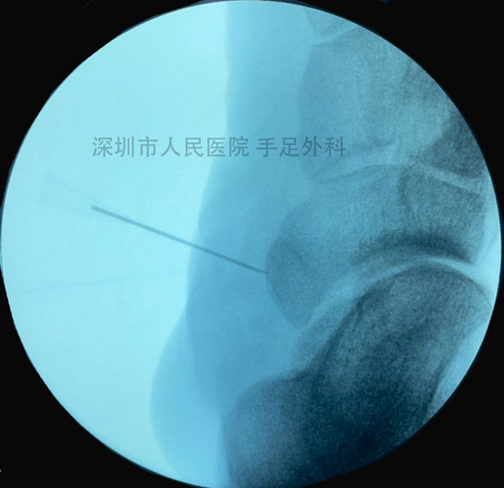

图6:对于成人副舟骨痛患者,采用Kidner术,先定位副舟骨。